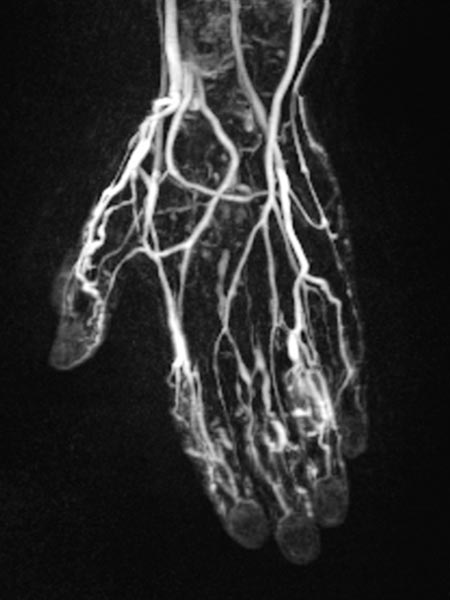

Dynamisch, kontrastmittelunterstützte MR-Angiographie der Hand, 30 s nach KM-Injektion intravenös.

Normale Handarterien, keine Fast-flow-Situation, keine erweiterten Arterien oder arteriovenöse Shunts.

Dynamisch, kontrastmittelunterstützte MR-Angiographie der Hand, 35 s nach KM-Injektion intravenös.

Bereits in dieser früharteriellen Phase erste Kontrastierung von Teilen der Malformation über kleine arteriovenöse Fisteln (AVF) vor allem an Daumen, Zeigefinger und Ringfinger.

Dynamisch, kontrastmittelunterstützte MR-Angiographie der Hand, 67 s nach KM-Injektion intravenös.

In dieser venösen Phase dann langsames geringes KM-Pooling innerhalb der venösen Malformation.